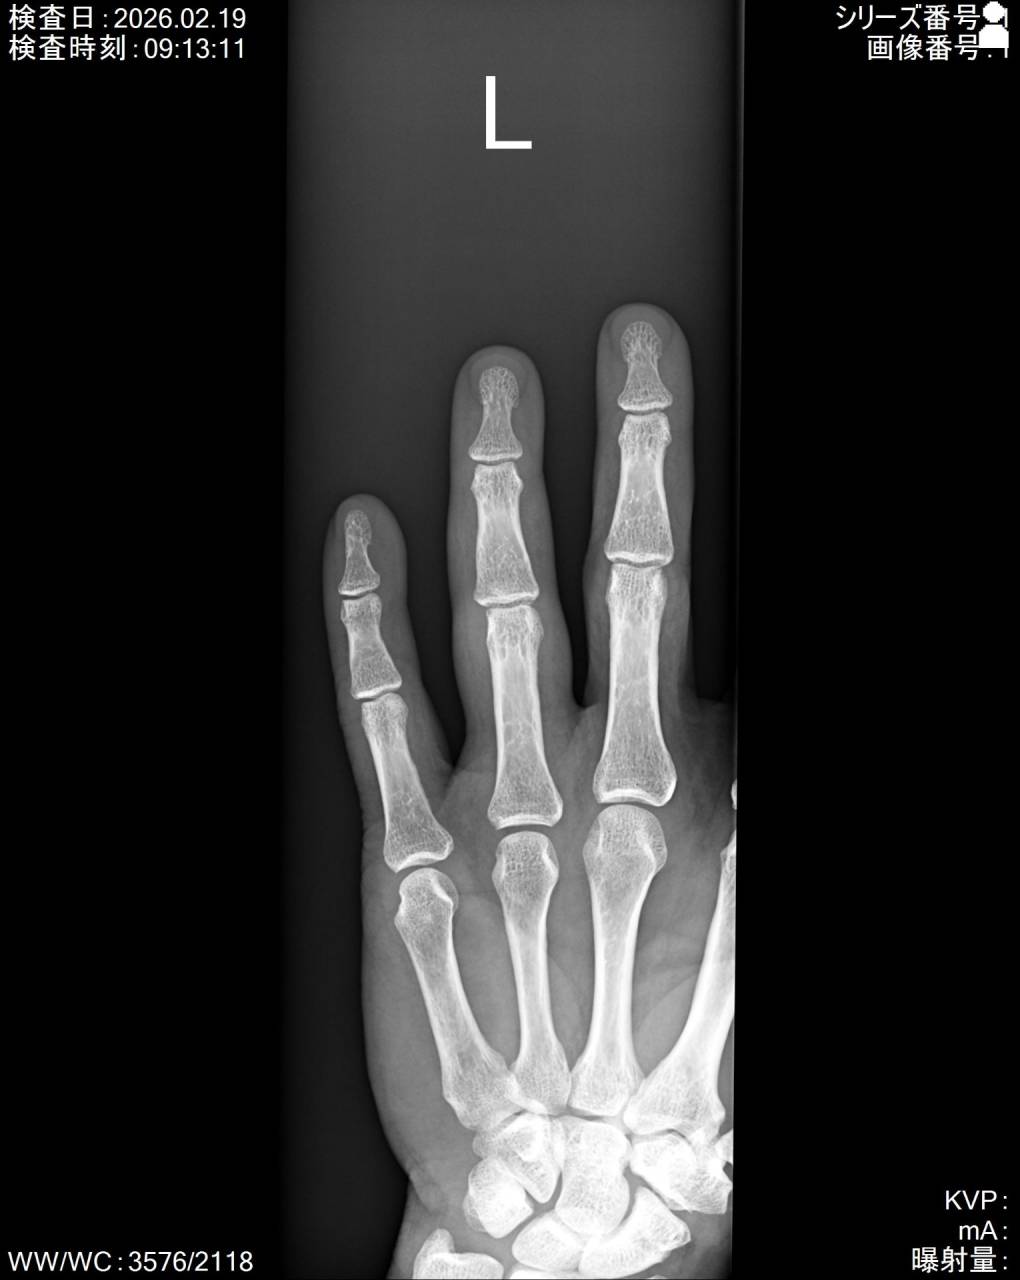

外見は傷もあり、傷の部分は水洗いにてキレイにしてあり、左第1、4、5指に腫脹(腫れ)と皮下出血がありました。

特に第4指は屈曲30度程しか曲げられず、一番痛みがあるとのことでした。

第4指の圧痛は基節骨骨頭と中節骨基部にあり、骨折の疑いもあったので超音波観察装置(エコー)にて確認を行いました。

エコーで画像を確認すると中節骨基部に骨折線があり骨折の疑いがあったので当整骨院が提携している病院にてレントゲン検査を依頼し、撮影した画像を確認すると左第4指中節骨基部に骨折が確認できたので骨折として施術を行っていきます。